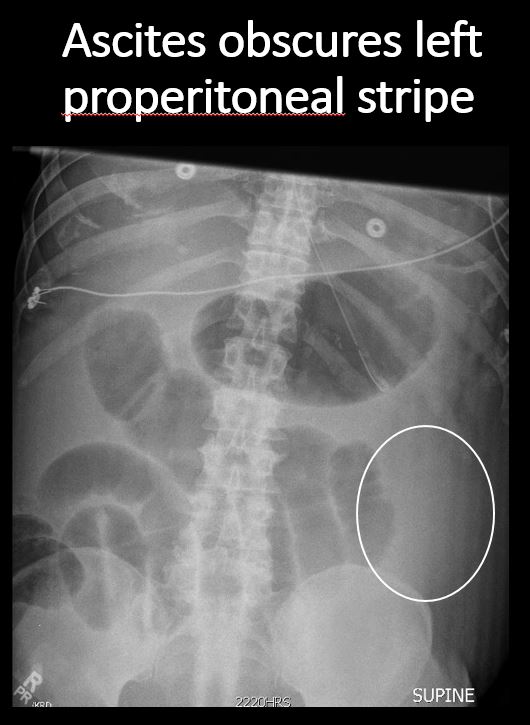

The right or left properitoneal stripe is obscured. |

No | NA |

The paracolic gutters are abnormal. |